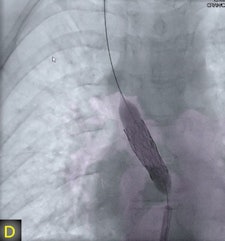

"The fusion of 3D reconstructions with live fluoroscopic images during catheterization may help to find the ideal fluoroscopic angulation during catheter-based interventions, to achieve difficult vascular crossings by the wire or the catheter, to choose the most appropriate material for catheterization, and to define and control optimized positioning of implants such as stents or valve prostheses," Glöckler and colleagues explained.

A pediatric cardiologist reconstructed cross-sectional images at 0.4-mm thickness in a 250 x 250 matrix format on a Leonardo DynaCT workstation (Siemens Healthcare) immediately after acquisition. FD-CT was used for diagnostic purposes in 32 of 62 cases, for intervention in 30 of 62 cases.

"One unique feature of FD-CT is the possibility of merging 3D reconstructions with the real-time fluoroscopic image," a potentially useful way to identify ideal C-arm angulations for achieving wire passage for atypical vascular crossings, and to optimally depict the implant position of coils, plugs, stents, and valves," Glöckler and colleagues wrote. "In fact, image fusion of 3D reconstructed FD-CT images with the live fluoroscopic image was frequently rated as 'very useful' (57.4%)."